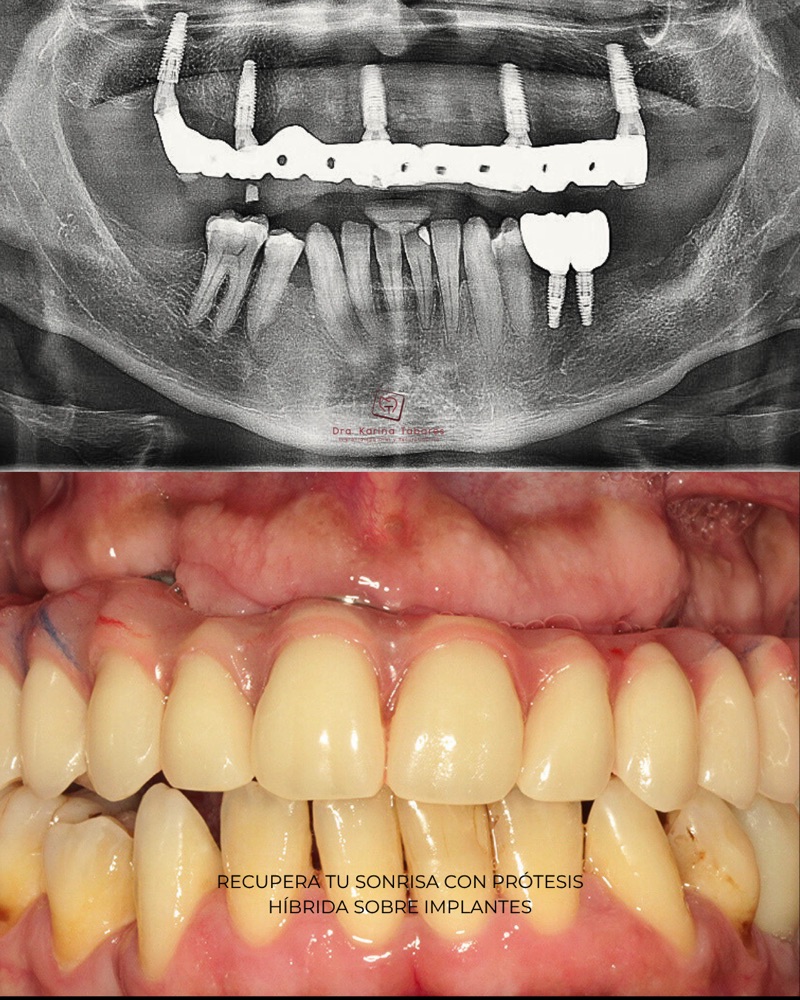

Antes y después

Cientos de pacientes han confiado en el equipo de la Dra. Karina Tabares y hoy comparten experiencias reales que han transformado sus vidas.